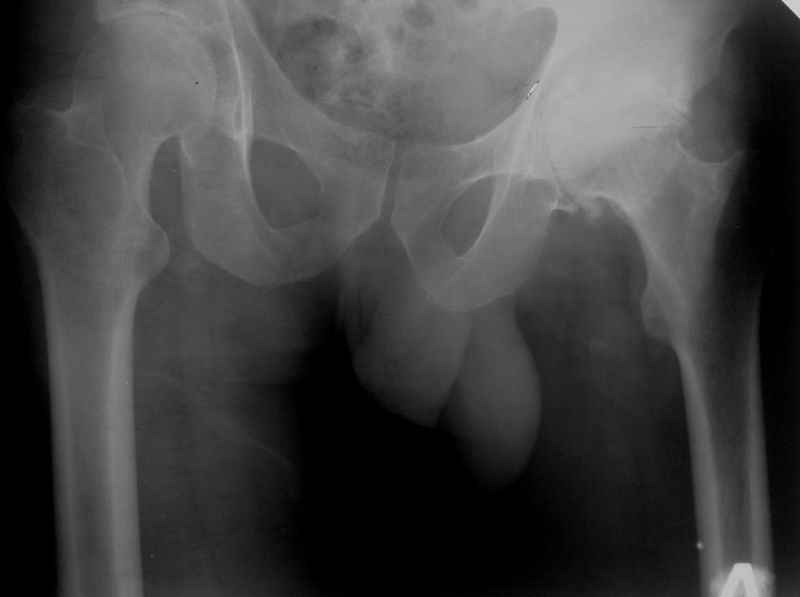

Доступ по Хардингу. Головка действительно S.

Чашка конечно же Variocup(Varioloc - ножка). После "погружения" чашки головку скорее всего придется менять на M или L.

Исходный сустав в приложении.